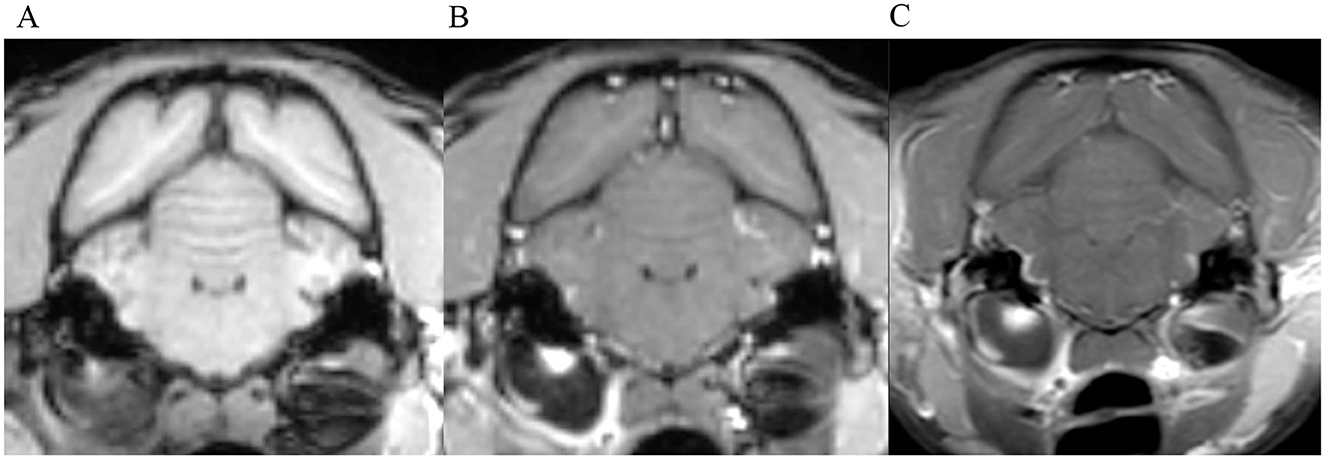

Figure 3. Transverse images at the level of the tympanic bullae. Example of perfect inter-observer agreement in the FS-TSE-T1W sequence in a cat. (A) is the T1W-pre-contrast image. 5/5 observers did not detect meningeal enhancement in the 3D-GRE-T1W (B), but agreed on detection in the FS-TSE-T1W (C). Meningeal enhancement was graded as focal and mild by all observers.

Figure 4. Transverse images at the level of the tympanic bullae. Example of perfect inter-observer agreement in the FS-TSE-T1W sequence in another cat. (A) is the T1W-pre-contrast image. 4/4 observers did not detect meningeal enhancement in the 3D-GRE-T1W (B), but agreed on detection in the FS-TSE-T1W (C). 3 observers graded it as focal and mild, while 1 observer graded it as focal and moderate enhancement.